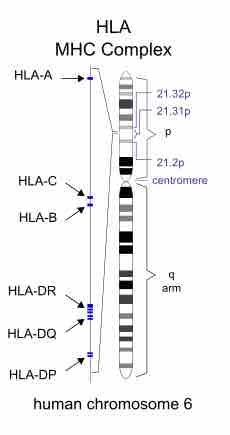

T cells play a central role in cell-mediated immune response through the use of the surface T cell receptor to recognize peptide antigens.

The T Cell Receptor (TCR) found on the surface of T cells is responsible for recognizing antigens.

Adaptive immunity is stimulated by exposure to infectious agents and recruits elements of the immunoglobulin superfamily.